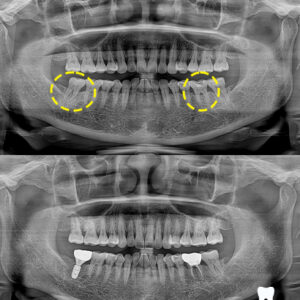

울산삼산치과 구치부 임플란트를 통한 저작 회복

울산삼산치과 구치부 임플란트를 통한 저작 회복 안녕하세요! 하나치과입니다~:) ​ 어금니 상실을 보완하는 가장 보편적이고 효과적인 방법으로는 임플란트가 꼽히는데요. ​ 인공치근을 잇몸뼈에 식립하고 그 위에 보철물을 올려 자연치처럼 가능하도록 만드는 방식으로 인접 치아를 손상시키지 않아 장기적으로도 구강 건강 유지에 유리합니다. ​ 하지만 이는 앞니보다 더 까다로운 시술로 위턱의 경우 상악동, 아래턱은 더보기…